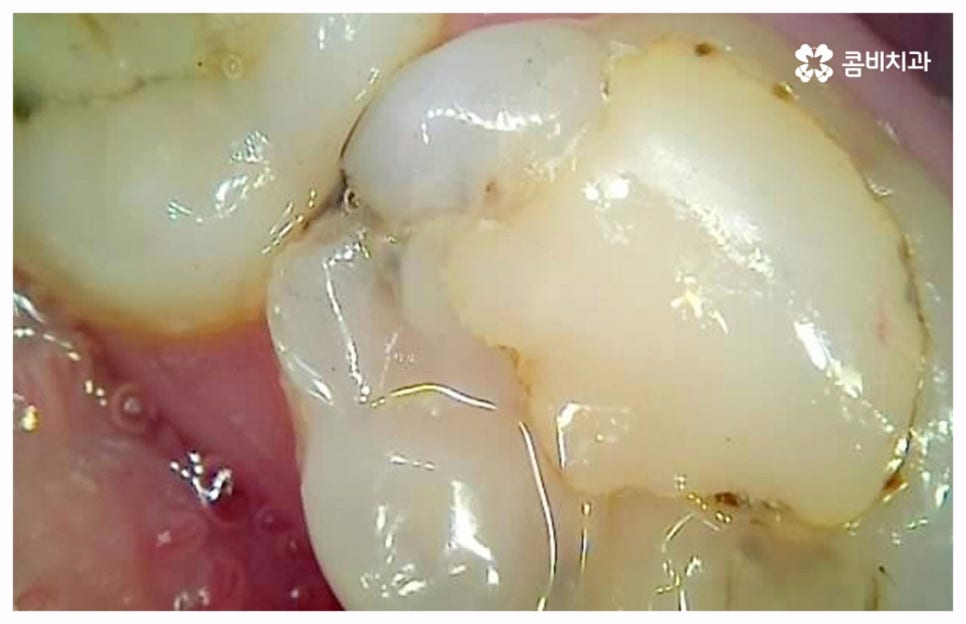

급성치수염에 대한 치료는 보통 안쪽까지 침투한 세균을 깨끗하게 긁어내고 염증 및 괴사된 치수 부분을 삭제한 다음 뿌리관(근관)을 소독하고 치과 충전물로 밀봉하는 신경 치료를 통해 이루어지는데, 이렇게 신경 치료를 진행하고 나서 후속 치료로서 남아있는 자연 치아를 보호하고 저작 기능을 제대로 수행할 수 있도록 하기 위해 주변 치아와 크기, 높이 등을 맞추어 딱 맞게 제작한 보철물을 덮어씌우는 크라운 치료를 해 주는 것이 자연 치아를 보다 오랜기간 동안 건강하게 사용할 수 있도록 하는데 크게 도움이 된다고 할 수 있어요. 경우에 따라서 앞니의 경우 신경관이 많지 않기 때문에 레진으로 치료를 마무리하는 경우도 있으니 참고해 주시면 좋을 것 같아요.

이 때 신경 치료가 끝나면 보통 통증이 사라지기 때문에 추후 시간적인 부분, 금전적인 이유 등 여러 가지 사정들로 인해서 크라운 치료가 필수적이지 않으면 신경 치료만 받고 끝마쳐도 되는지 문의를 주시는 분들이 있는데요. 크라운 치료를 해 준 치아의 경우 밀봉만 한 치아 보다 훨씬 수명이 길기 때문에 환자분들께서 크라운 치료의 필요성에 대해서 잘 인지하실 필요가 있어요. 이것은 신경 치료를 받은 치과 환자 4만 6000명을 분석한 미국 연구팀의 발표를 통해서도 알 수 있는데요. 이에 따르면 근관 속의 손상된 치수를 긁어내고 소독한 뒤 충전물로 밀봉한 치아의 경우 평균 생존 기간이 11.1년이었던 것에 반해서 추후 크라운까지 씌운 치아의 평균 수명은 약 20년으로 길어졌다고 하니 의료진과 충분히 상담하셔서 자신의 상황에 잘 맞는 보철물로 크라운 치료까지 끝마치시길 권유드리고 있습니다.